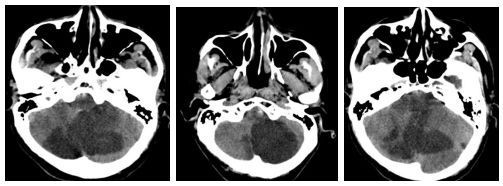

"很多患者像张女士一样,长期被误诊为颈椎病,"王医生说,"前庭性偏头痛的确诊需要专业的神经内科评估,包括详细询问病史、前庭功能检查和必要的影像学检查。"